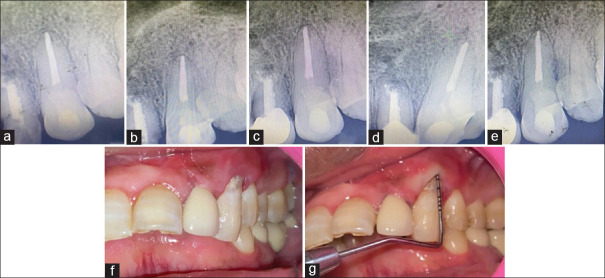

牙齿吸收;内部和外部,偶尔发生作为牙槽器感染的炎症反应。根据吸收的类型、病因和发现根吸收缺陷的阶段,提出了不同的治疗方案。本病例报告展示了通过使用生物陶瓷密封剂(BioRoot RCS)的非手术根管治疗和使用Biodentine重建吸收缺陷来治疗广泛的炎症性内外根吸收。在1、3、6和12个月的随访中,临床和影像学证据显示根尖周愈合、牙根吸收停止和牙周再植的迹象。锥束计算机断层扫描在诊断、决策和治疗计划中起着至关重要的作用,从而成功地管理这些有牙髓-牙周受累的病例。在12个月的随访中,临床和放射学结果支持,使用生物陶瓷材料可以成功地治疗广泛的牙根吸收和牙周组织累及的病例。

Tooth resorption; both internal and external, occasionally occurs as an inflammatory response of the dentoalveolar apparatus to infection. Depending on the type of resorption, etiology, and the stage at which root resorption defect is detected, different treatment regimens have been proposed. This case report demonstrates the management of extensive inflammatory combined internal and external root resorption by nonsurgical endodontic therapy using a Bioceramic sealer (BioRoot RCS) and surgical reconstruction of resorptive defect using Biodentine. On follow-up at 1, 3, 6, and 12 months, clinical and radiographic evidence revealed signs of periapical healing, arrested root resorption, and periodontal reattachment. The inclusion of cone beam computed tomography plays a crucial role in diagnosis, decision-making, and treatment planning and thus successful management of such cases having Endodontic-Periodontal involvement. As supported by clinical and radiographic findings at 12-month follow-up, treatment of cases with extensive root resorption and associated involvement of periodontium can be successfully done using bioceramic materials.